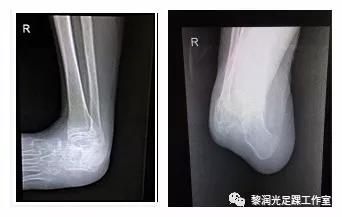

4. Ilizarov技术(外架缓慢矫正)

随着Ilizarov外架技术的发展,中枢神经系统损伤后足踝部畸形也可以应用Ilizarov外架进行矫正,Ilizarov技术更为微创,矫形更为充分,但是需要携带外架的时间较长。

本例病人为脊髓损伤后出现马蹄内翻足,通过Ilizarov外架技术矫正畸形。